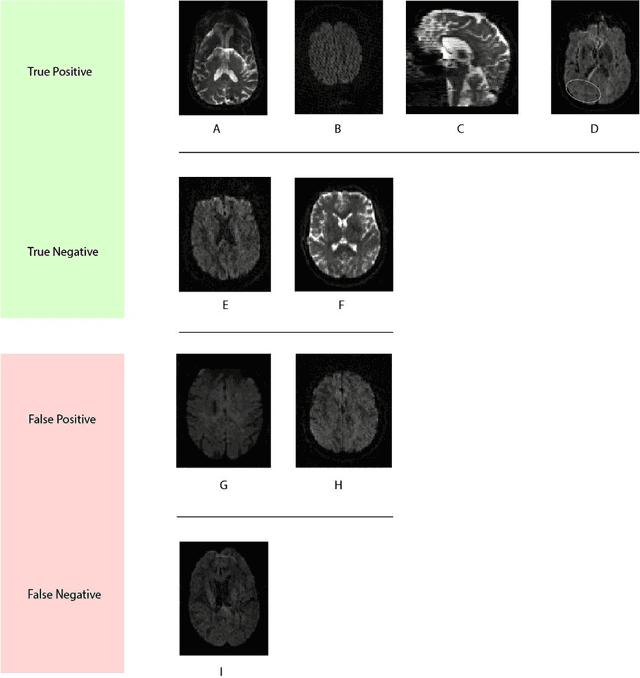

Abstract:Artifacts are a common occurrence in Diffusion MRI (dMRI) scans. Identifying and removing them is essential to ensure the accuracy and viability of any post processing carried out on these scans. This makes QC (quality control) a crucial first step prior to any analysis of dMRI data. Several QC methods for artifact detection exist, however they suffer from problems like requiring manual intervention and the inability to generalize across different artifacts and datasets. In this paper, we propose an automated deep learning (DL) pipeline that utilizes a 3D-Densenet architecture to train a model on diffusion volumes for automatic artifact detection. Our method is applied on a vast dataset consisting of 9000 volumes sourced from 7 large clinical datasets. These datasets comprise scans from multiple scanners with different gradient directions, high and low b values, single shell and multi shell acquisitions. Additionally, they represent diverse subject demographics like the presence or absence of pathologies. Our QC method is found to accurately generalize across this heterogenous data by correctly detecting 92% artifacts on average across our test set. This consistent performance over diverse datasets underlines the generalizability of our method, which currently is a significant barrier hindering the widespread adoption of automated QC techniques. For these reasons, we believe that 3D-QCNet can be integrated in diffusion pipelines to effectively automate the arduous and time-intensive process of artifact detection.